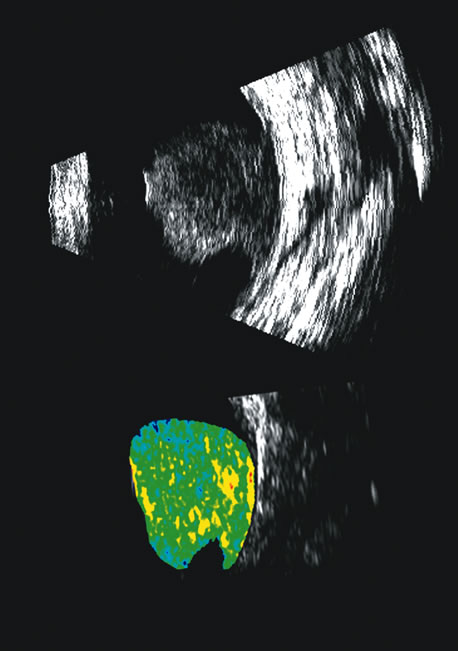

The representation of volume and three-dimensional perspectives of the diseased vitreous, retinal detachment, choroidal detachment, and tumors can add to presurgical conceptualization and is critical to characterization of tumors in relation to prediction of lethality.45 In addition, volume measurement of the choroid permits studies of both surgical and physiologic rates of clearance of hemorrhage, whereas vitreous volume studies can make the estimation of gas or other vitreous substitutes for replacement more accurate (Fig. 25).

Fig. 25. A 3D reconstruction of serial scans of a posterior pole melanoma taken with a 10 MHz transducer (left) shows the extent and relative asymmetry of the tumor within the vitreous cavity. 3D biometry can be useful for treatment planning for radiotherapy and brachytherapy. 3D reconstructions of 50 MHz serial ultrasound scans and parameter images of a melanoma involving the ciliary body and anterior uvea (center, right) before and after treatment with combined ultrasound hyperthermia and brachytherapy. Changes in the concentration of ultrasound scattering elements related to tissue necrosis are seen as color scale in the pre- and postimage region of the tumor shifts, from blue, indicating relatively low acoustic concentration, to yellow and green, indicating higher concentrations of scatterers.

Spectral parameter imaging, a digital signal processing technique that examines the frequency content of backscattered ultrasound signals, has been shown to be predictive of increased lethality in certain patients and also to be useful in the in-vivo identification of high-risk melanomas for treatment staging.46–48 The shape, density, orientation, and number of scattering elements in a region influence not only the relative amplitude or brightness of a pixel on B-scan but the frequency content of the signal returned to the transducer.19 The concept of differentiating tissue backscatter in a quantitative manner rather than in simple qualitative descriptions of hypo-, iso-, and hyperechoic variations in gray scale allows for maximum use of information available in the digital ultrasonograms. These techniques can be extended to examining the functional anatomy of the eye as well as disease states other than solid tumors (Fig. 26).

Fig. 26. A gray-scale B-scan of a large collar-button melanoma (top) showing a relatively isoechoic button and base with some differences in internal speckle noted. The companion serial plane spectral parameter image (bottom) shows local differences in the size of ultrasound scatterers within the tumor, with size range increasing from blue to red.